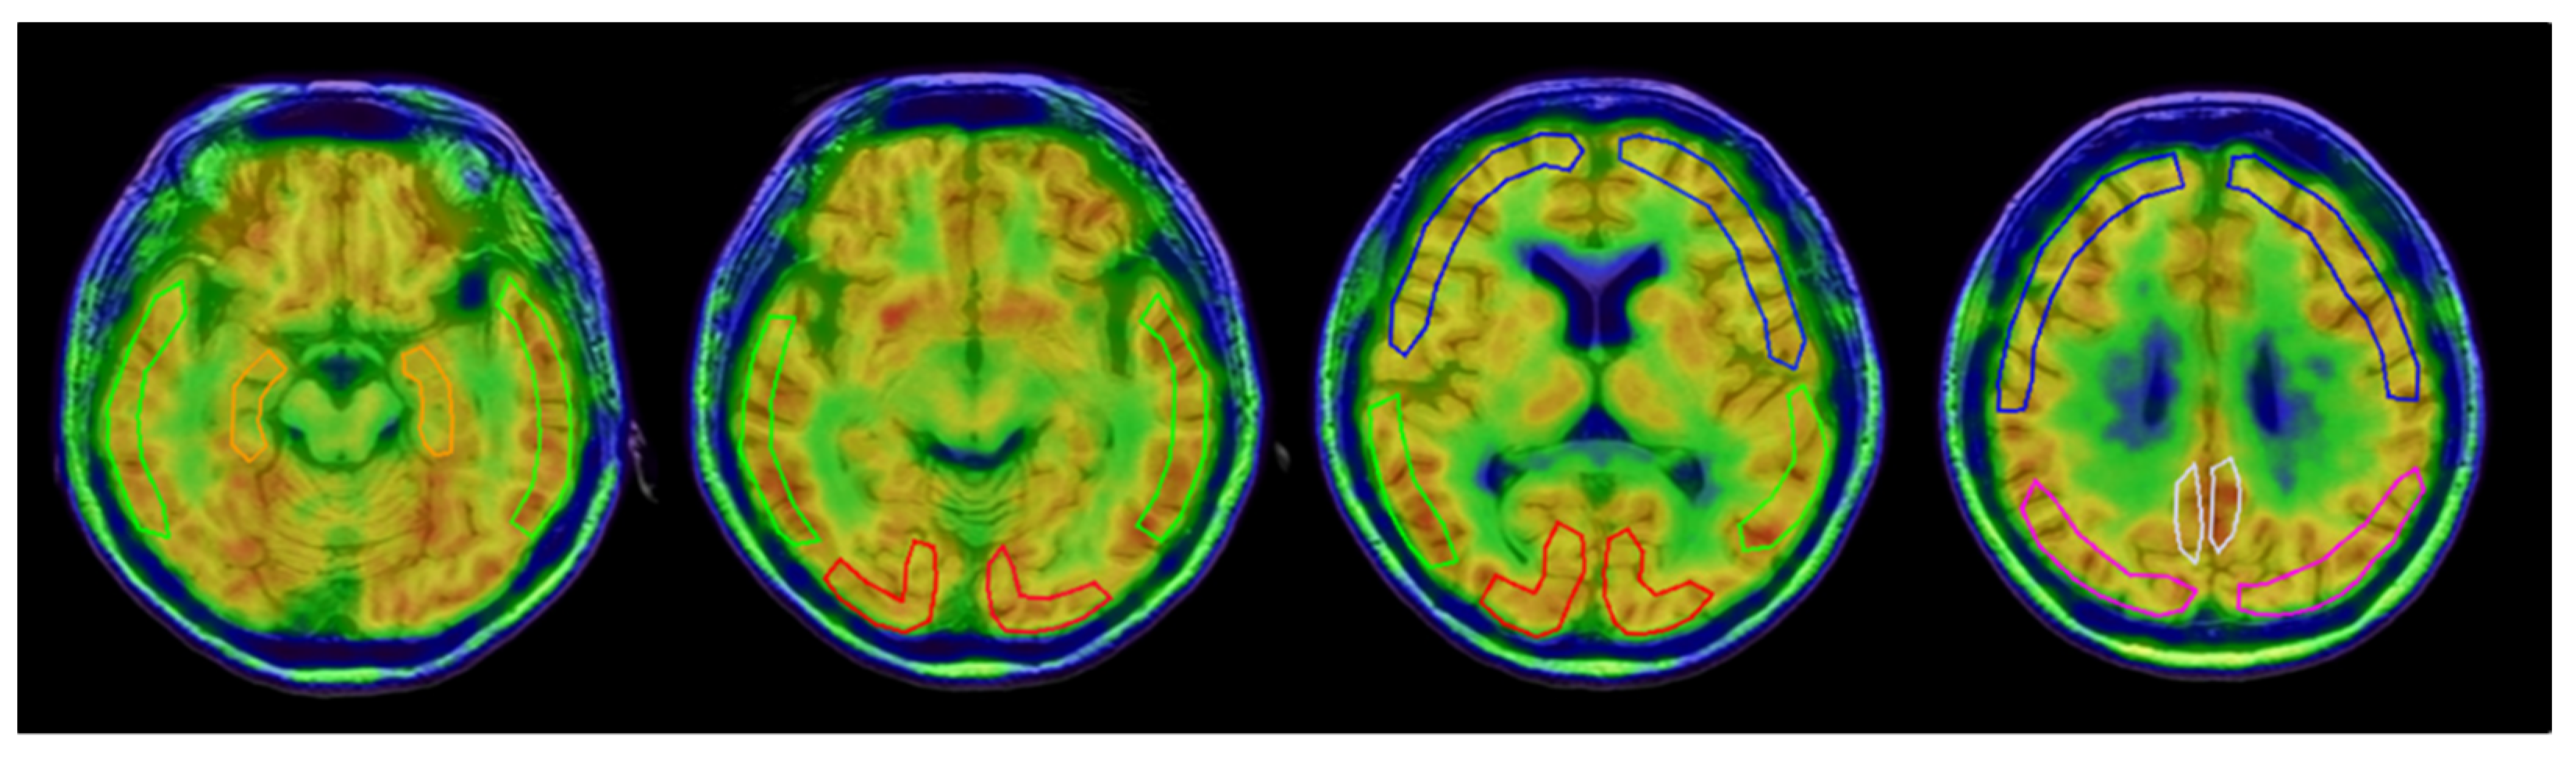

- Okazawa, H.; Ikawa, M.; Jung, M.; Maruyama, R.; Tsujikawa, T.; Mori, T.; Rahman, M.G.M.; Makino, A.; Kiyono, Y.; Kosaka, H. Multimodal analysis using [11C]PiB-PET/MRI for functional evaluation of patients with Alzheimer’s disease. EJNMMI Res. 2020, 10, 30. [Google Scholar] [CrossRef]